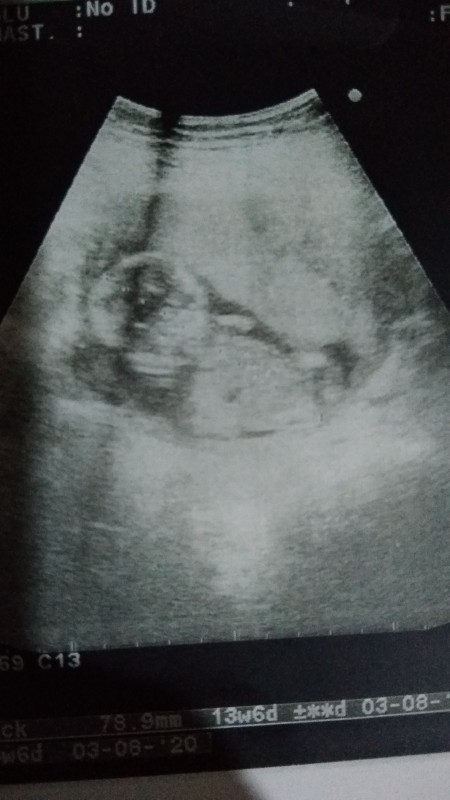

ccinsiyetini tahmin edebilir misiniz ?

Bu utrason görüntüsü çok kötü

Bana da ilk bakışta kız gibi geldi

Erkek bence:

bncede kız gibi canim :)